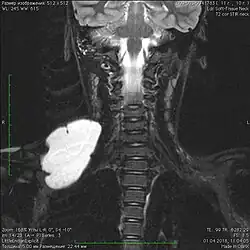

В литературе приводится множество наблюдений различных локализаций общих (кистозных) лимфатических мальформаций. Описаны следующие области: голова и шея, нижние конечности, средостение, матка, поджелудочная железа, мошонка, твёрдая мозговая оболочка, оболочки яичка, сердце. В 50-75 % лимфатические мальформации встречаются в области головы и шеи[10][11], в 27 % они встречаются в области туловища, в 24 % — на конечностях. Висцеральные лимфатические мальформации определяются очень редко[12][13].

Пороки развития лимфатических сосудов в области головы и шеи чаще всего определяются при рождении или в первые годы жизни ребёнка, в возрасте до одного года в 60-80 % случаев[6]. Основными методами визуализации лимфатической мальформации являются ультразвуковое исследование (УЗИ) и магнитно-резонансная томография (МРТ). Данные исследования позволяют определить площадь и объём патологических тканей, размеры кист, топографию образования.

Лимфатические мальформации в области головы и шеи, диагностируемые внутриутробно, обычно имеют огромные размеры, угрожающие жизни матери и ребёнка. В связи с этим заранее формируется специальная бригада врачей для оказания реанимационных мероприятий, в частности для предотвращения острой дыхательной недостаточности у новорождённого. За рубежом комплекс данных мер носит название EXIT (The ex utero intrapartum therapy procedure)[16].